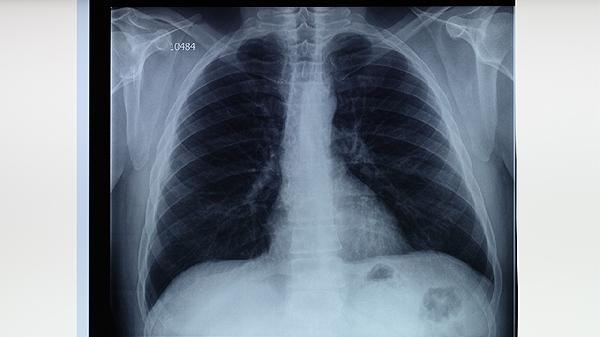

4、影像学检查

胸部X线可发现典型的上叶尖后段浸润影、空洞等改变,CT能更清晰显示早期微小病灶。但影像表现需与肺炎、肺癌等疾病鉴别,单纯影像学不能作为确诊依据。部分免疫抑制患者可能缺乏典型影像特征,需结合实验室检查。